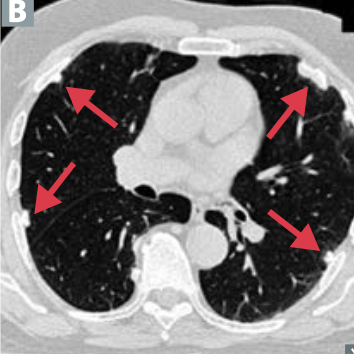

Where does bronchioloalveolar carcinoma originate? What would chest X-ray show?

A

Type II pneumocytes or terminal bronchioles

Peripheral pneumonia-like consolidation rather than mass lesion